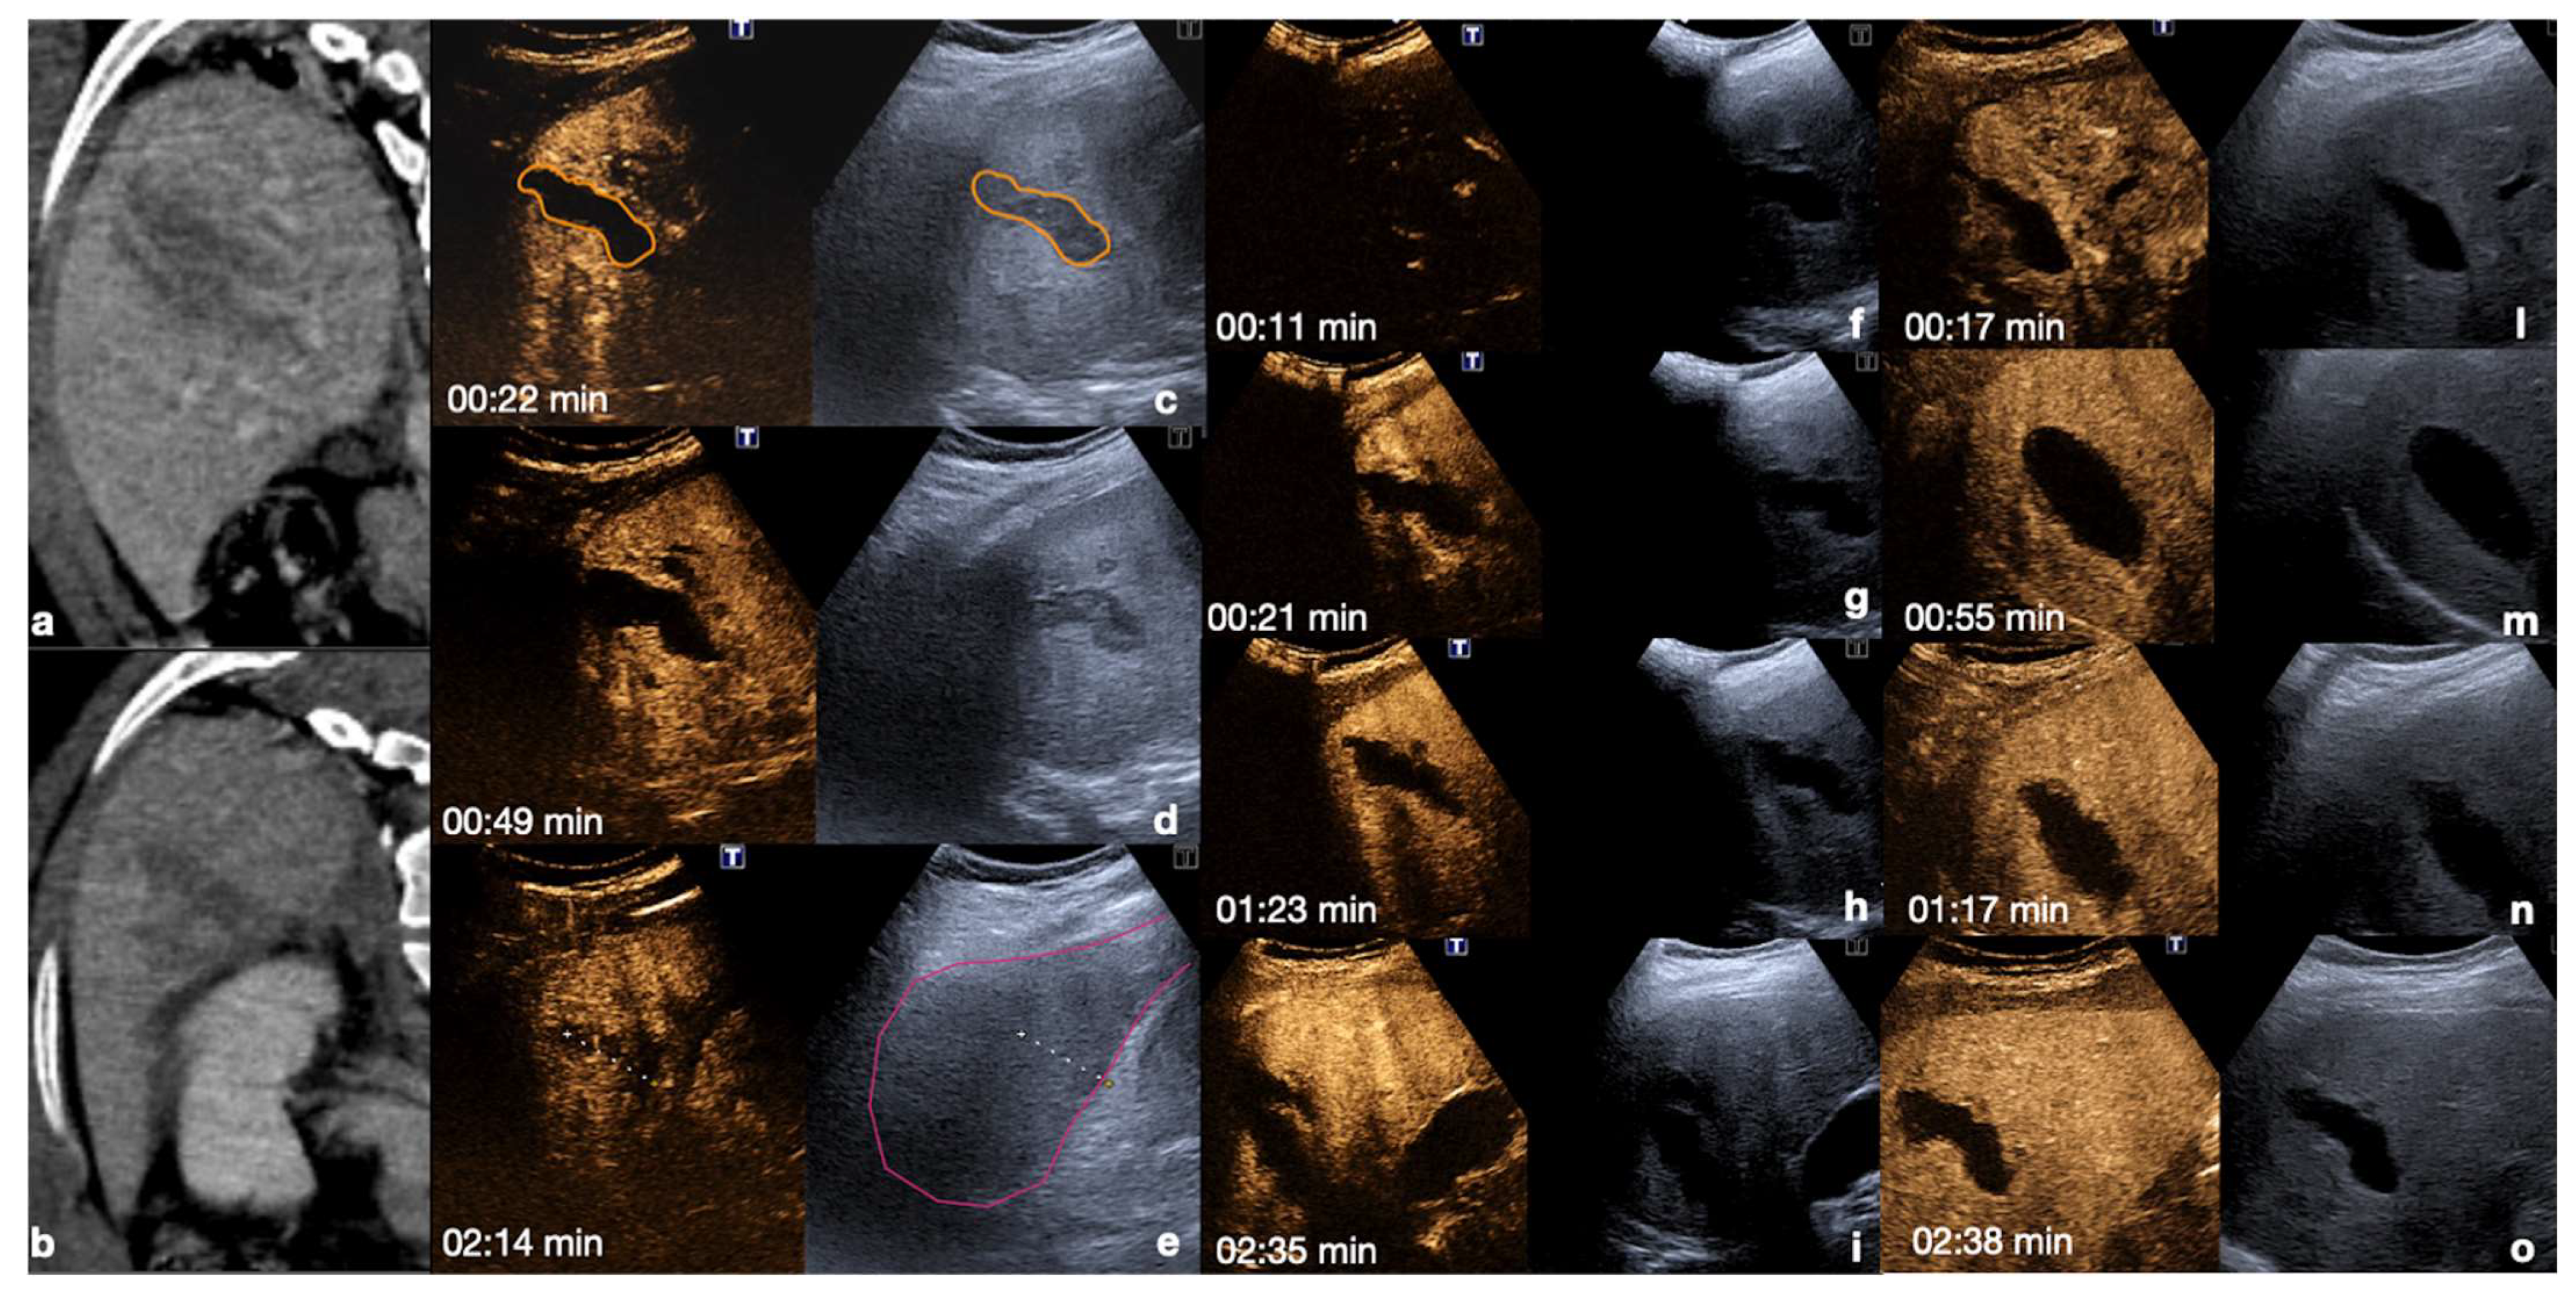

Figure 14.

Admission CT (a,b) and follow-up CEUS (c–o) of a 35−year-old blunt trauma patient with multiple hepatic lacerations. Follow-up CEUS was performed 3 days (c–e), 11 days (f–i), and 20 days (l–o) after the admission CT. Note at CEUS the progressive enhancement of the liver parenchyma in the different phases. The parenchymal lacerations appear as non-enhancing bands (c, orange line), some of them reaching the liver capsule (pink line) (e,i). In the follow-up, it is important to look for possible vascular injuries (absent in this case) in the early arterial phase (f,l). Parenchymal lacerations appear progressively better demarcated, and more hypoechoic. Adopted from ref. [30], 2021, Iacobellis, F.; et al.